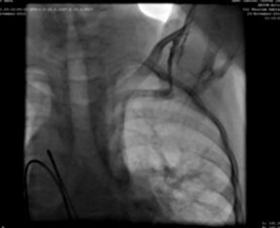

We used a 9F delivery sheath, which was advanced over and placed in the descending aorta over the super-stiff guidewire. A AnıTm cone shape PDA occluder 14/12 mm, was attached to the delivery cable and progressed across the delivery sheath. The placement of the occlude was proper with no residual flow.

Cerrahi başarı, ciddi intraoperatif komplikasyonlar yok, oklüzyondan sonra 24 saat ekokardiyografi iyi yerleştirme, kusurda artık şant göstermiyor.